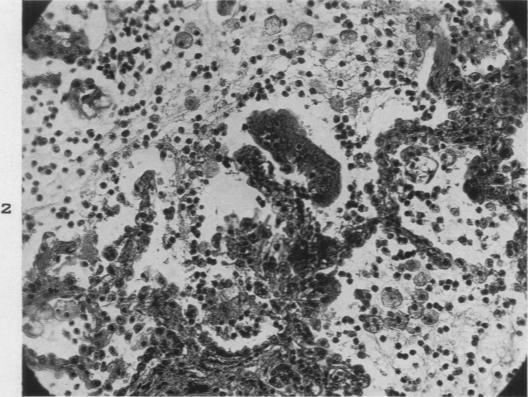

So-Called Pulmonary Adenomatosis and "Alveolar Cell Tumors": Report of a Case.

Am J Pathol. 1947 May;23(3):413-27.